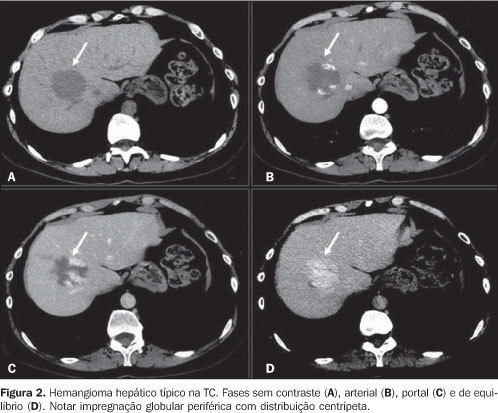

Hemangioma hepático na TC

Tem enchimento centrípeto e lento - retenção do contraste quando acaba fase arterial